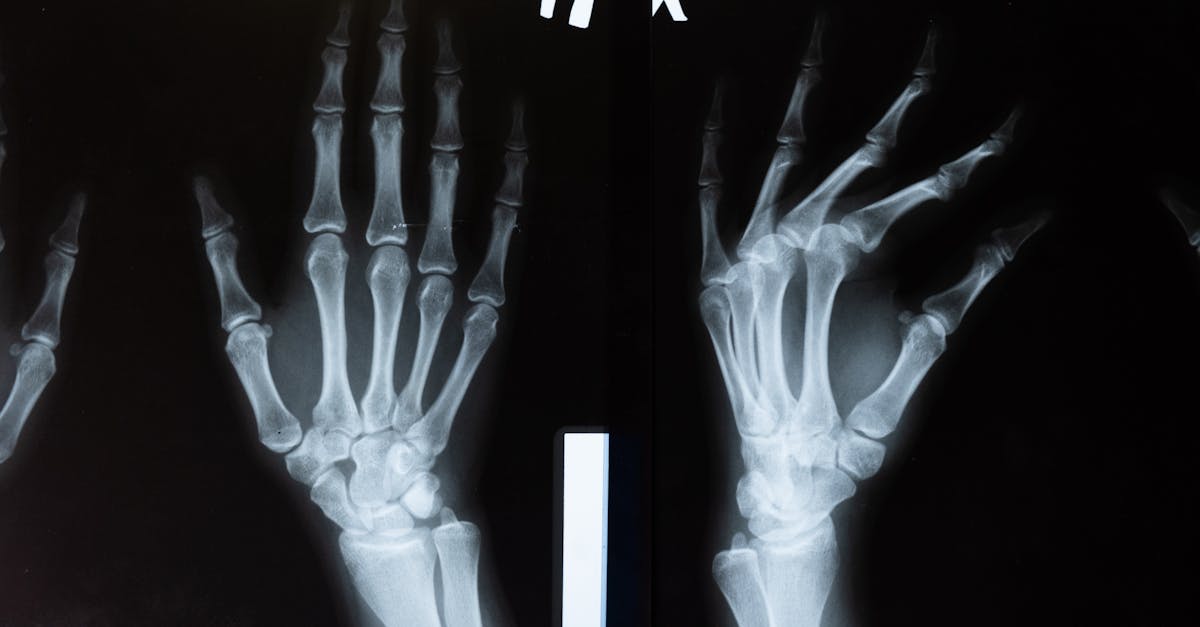

Imaging plays a crucial role in monitoring the progress of various medical treatments. It allows healthcare professionals to visualize the internal changes in a patient's body over time, providing valuable insights into the effectiveness of the treatment being administered. By utilizing imaging techniques such as X-rays, MRI, and CT scans, doctors can track the response of tumors to chemotherapy, evaluate the healing of fractures, or observe the reduction in inflammation post-treatment.

Imaging techniques can detect various abnormalities, diseases, injuries, and changes within the human body by creating visual representations of internal structures and functions.

Imaging is crucial for monitoring treatment progress by allowing healthcare providers to visualize changes in the size, shape, and characteristics of tumors, infections, or other conditions over time.